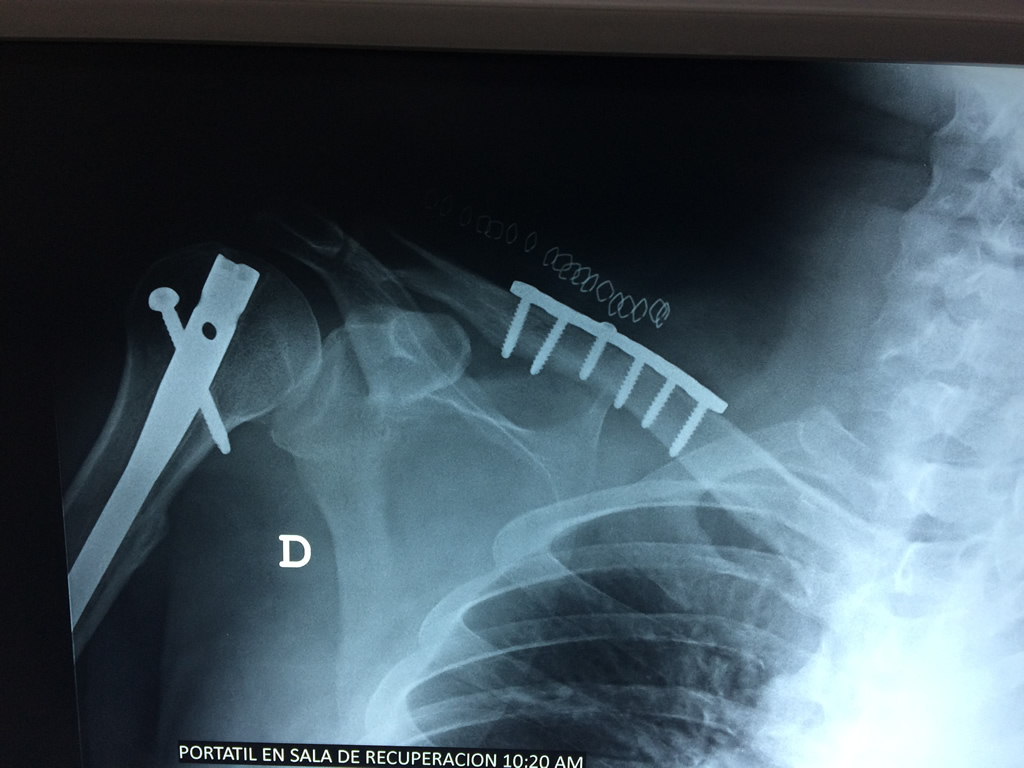

Húmero - Clavícula

La clavícula es un hueso largo, con forma de "S" itálica, situado en la parte anterosuperior del tórax. Junto con la escápula forman la cintura escapular. Se puede palpar por toda su longitud y se extiende del esternón al acromion de la escápula, siguiendo una dirección oblicua lateral y posterior.

Se considera el único medio de unión entre el miembro superior y el tórax. A pesar de su aspecto, similar al de un hueso largo, posee una estructura semejante a la de un hueso plano, ya que carece de epífisis y de diáfisis, lo que la harían entrar dentro de la clasificación de hueso largo. Carece de un canal medular propiamente dicho.